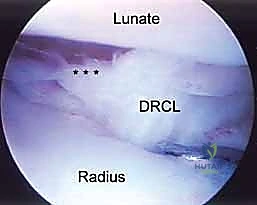

- Function: Indicated for evaluating the dorsal radiocarpal ligament (DRCL) and the palmar portion of the scapholunate interosseous ligament (SLIL). It provides a clear view of dorsal rim fragments for arthroscopic reduction of intra-articular distal radius fractures.

- Function: Indicated for visualizing and débriding palmar tears of the lunotriquetral ligament (LTIL). It aids in the repair or débridement of dorsally located TFCC tears, especially when triangulation from dorsal portals is difficult. It also assesses the dorsal radioulnar ligament, the ECU subsheath, and the radial TFCC attachment.